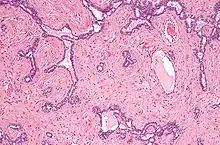

- Micrograph of the rete testis involved by seminoma. H&E stain.